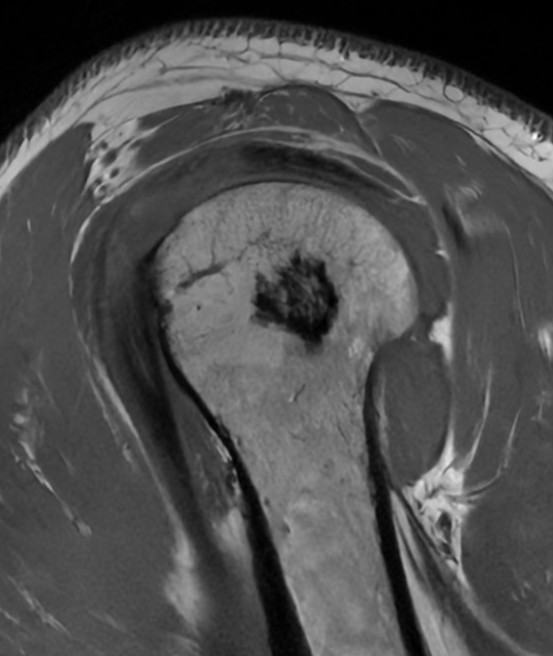

MRI

- Low signal on T1 and T2

- Do not enhance with contrast